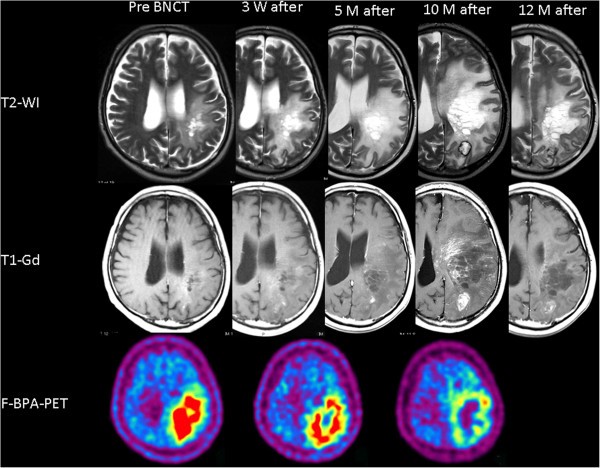

MRI显示病灶轻度增强,伴有轻度病灶周围水肿。同时用氟18标记的BPA正电子发射断层显像(F-BPA-PET)图像显示左顶额叶区域中显著的示踪剂吸收,示踪剂的病灶/正常(L / N)脑比例为6.0,表明该病灶是高度恶性的肿瘤。

根据我们最近针对复发性恶性神经胶质瘤RMG和脑膜瘤的治疗方案,BNCT用于该患者。简而言之,仅在中子辐照之前和期间(100 mg / kg / hr)在2小时内(200 mg / kg / hr)施用BPA。根据模拟确定中子辐照时间不超过峰值脑剂量的12.0 Gy-Eq(灰色当量)。中子照射期间血液中的10-B浓度为23.0百万分之一(ppm)。通过BNCT,最大脑剂量、最大肿瘤剂量和最小肿瘤剂量分别估计为11.4、118和36.1 Gy-Eq。在此,“ Gy-Eq”对应于生物学上等效的X射线剂量,该剂量将对肿瘤和正常大脑产生等效影响。